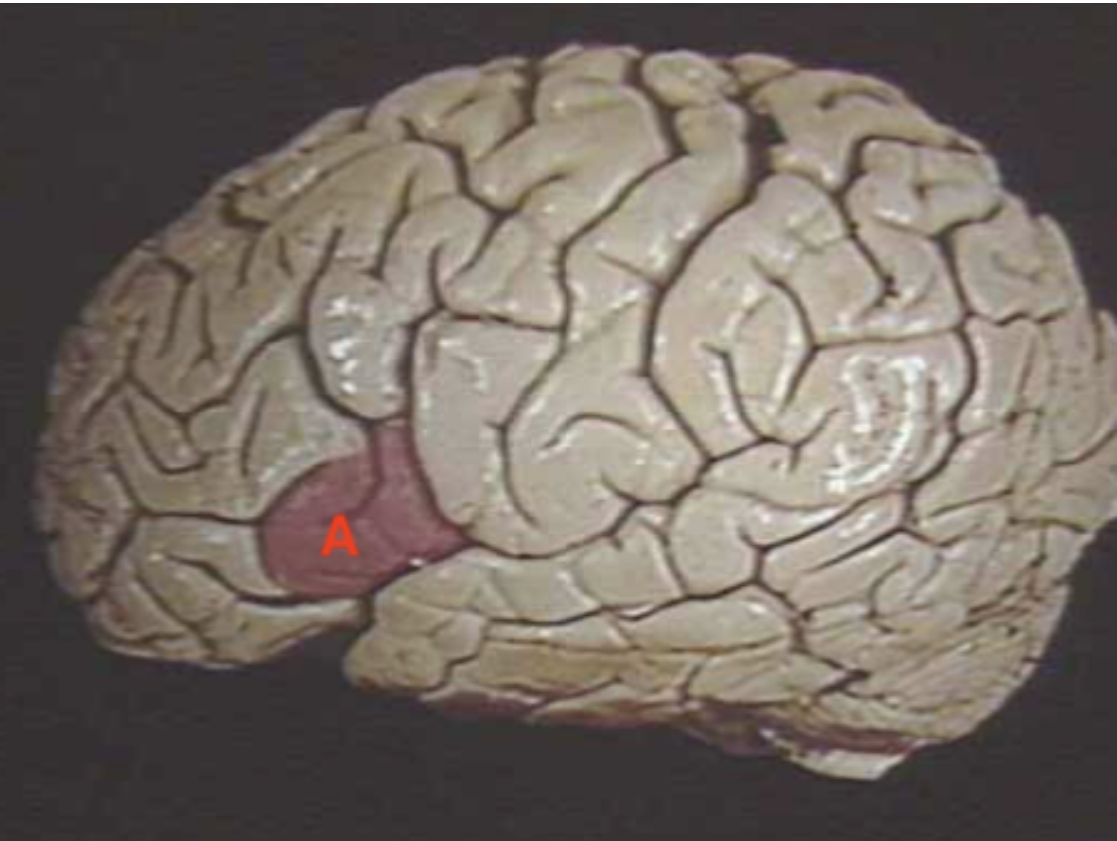

A

Broca’s Area